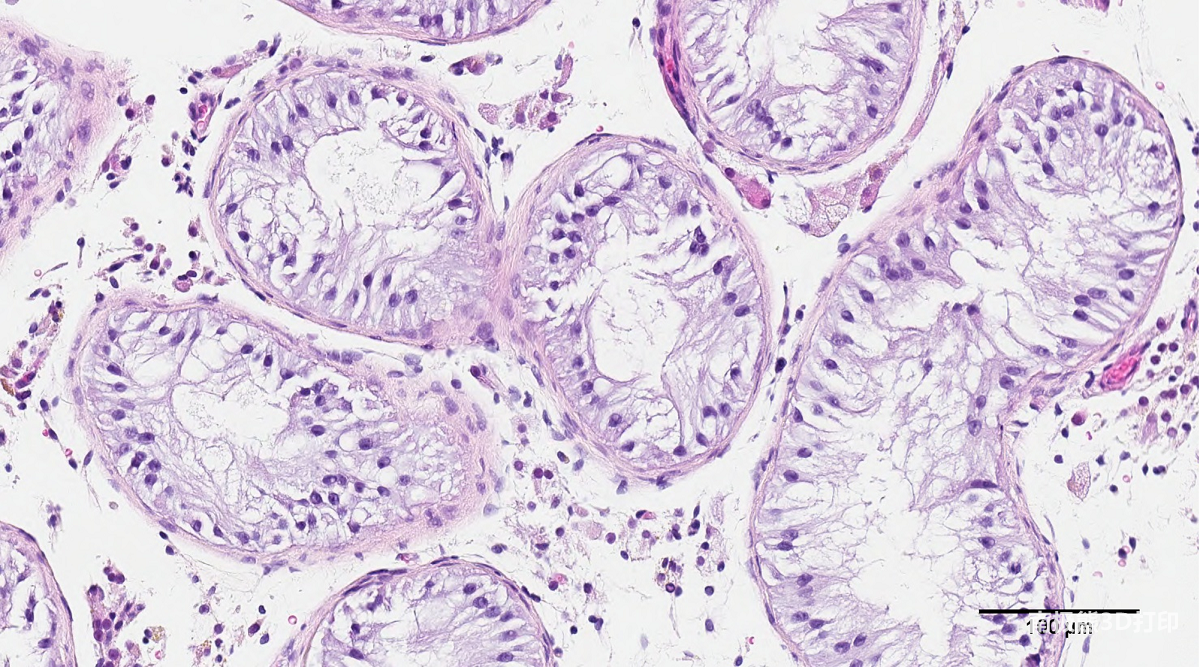

Researchers at the University of British Columbia (UBC) have completed the world’s first 3D analysis of human testicular cells

Printing the experiments, the team hopes the technology can be applied to the treatment of male infertility in the future.

He said: “We based on human anatomy, these cells3D printinginto a very specific structure, which can play a very good role in promoting sperm development. If successful, this could lead to new fertility treatments for couples who currently have no other options.”

More details of the study can be seen in the paper titled “Using Clinically Derived Human Tissue to 3D Bioprint Personalized Testicular Tubules Forin-Vitro Culturing. First Report”.